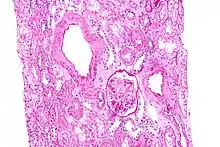

L’amylose rénale est de loin la plus précoce et la plus fréquente des complications

Biopsie rénale, à haute résolution, de dépôts amyloïdes.

La substance amyloïde de la maladie périodique est formée de fibrilles identiques à la protéine de l'amylose AA, et elle intéresse de manière diffuse la paroi de toutes les artérioles, sauf celles du système nerveux central ; cette répartition est dominée par la localisation rénale..

La phase néphrotique est caractérisée par l’apparition d’un syndrome néphrotique clinique et biologique. La confirmation histologique peut être apportée par la biopsie rénale, la biopsie rectale (positive dans 75 à 85 % des cas), voire par la biopsie médullaire.